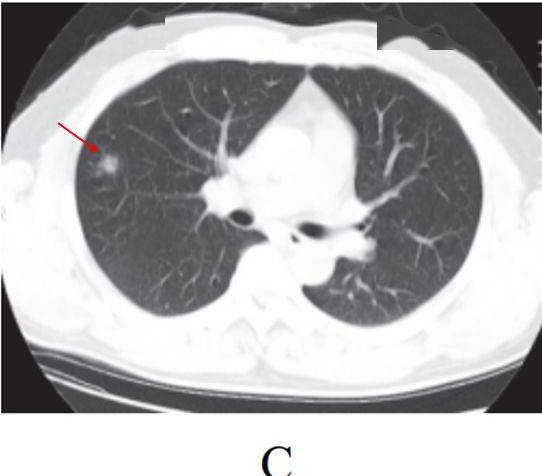

(一)病灶分布

病灶以 肺外围背侧为主,以两肺下叶为著,与胸膜常紧贴,提示新冠肺炎病变多首先侵犯皮层肺组织的细支气管及肺泡上皮, 病灶分布逐步从外周向中央扩展(图 2-1)

图2-1 早期病灶多数分布贴近胸膜( 共4张 )